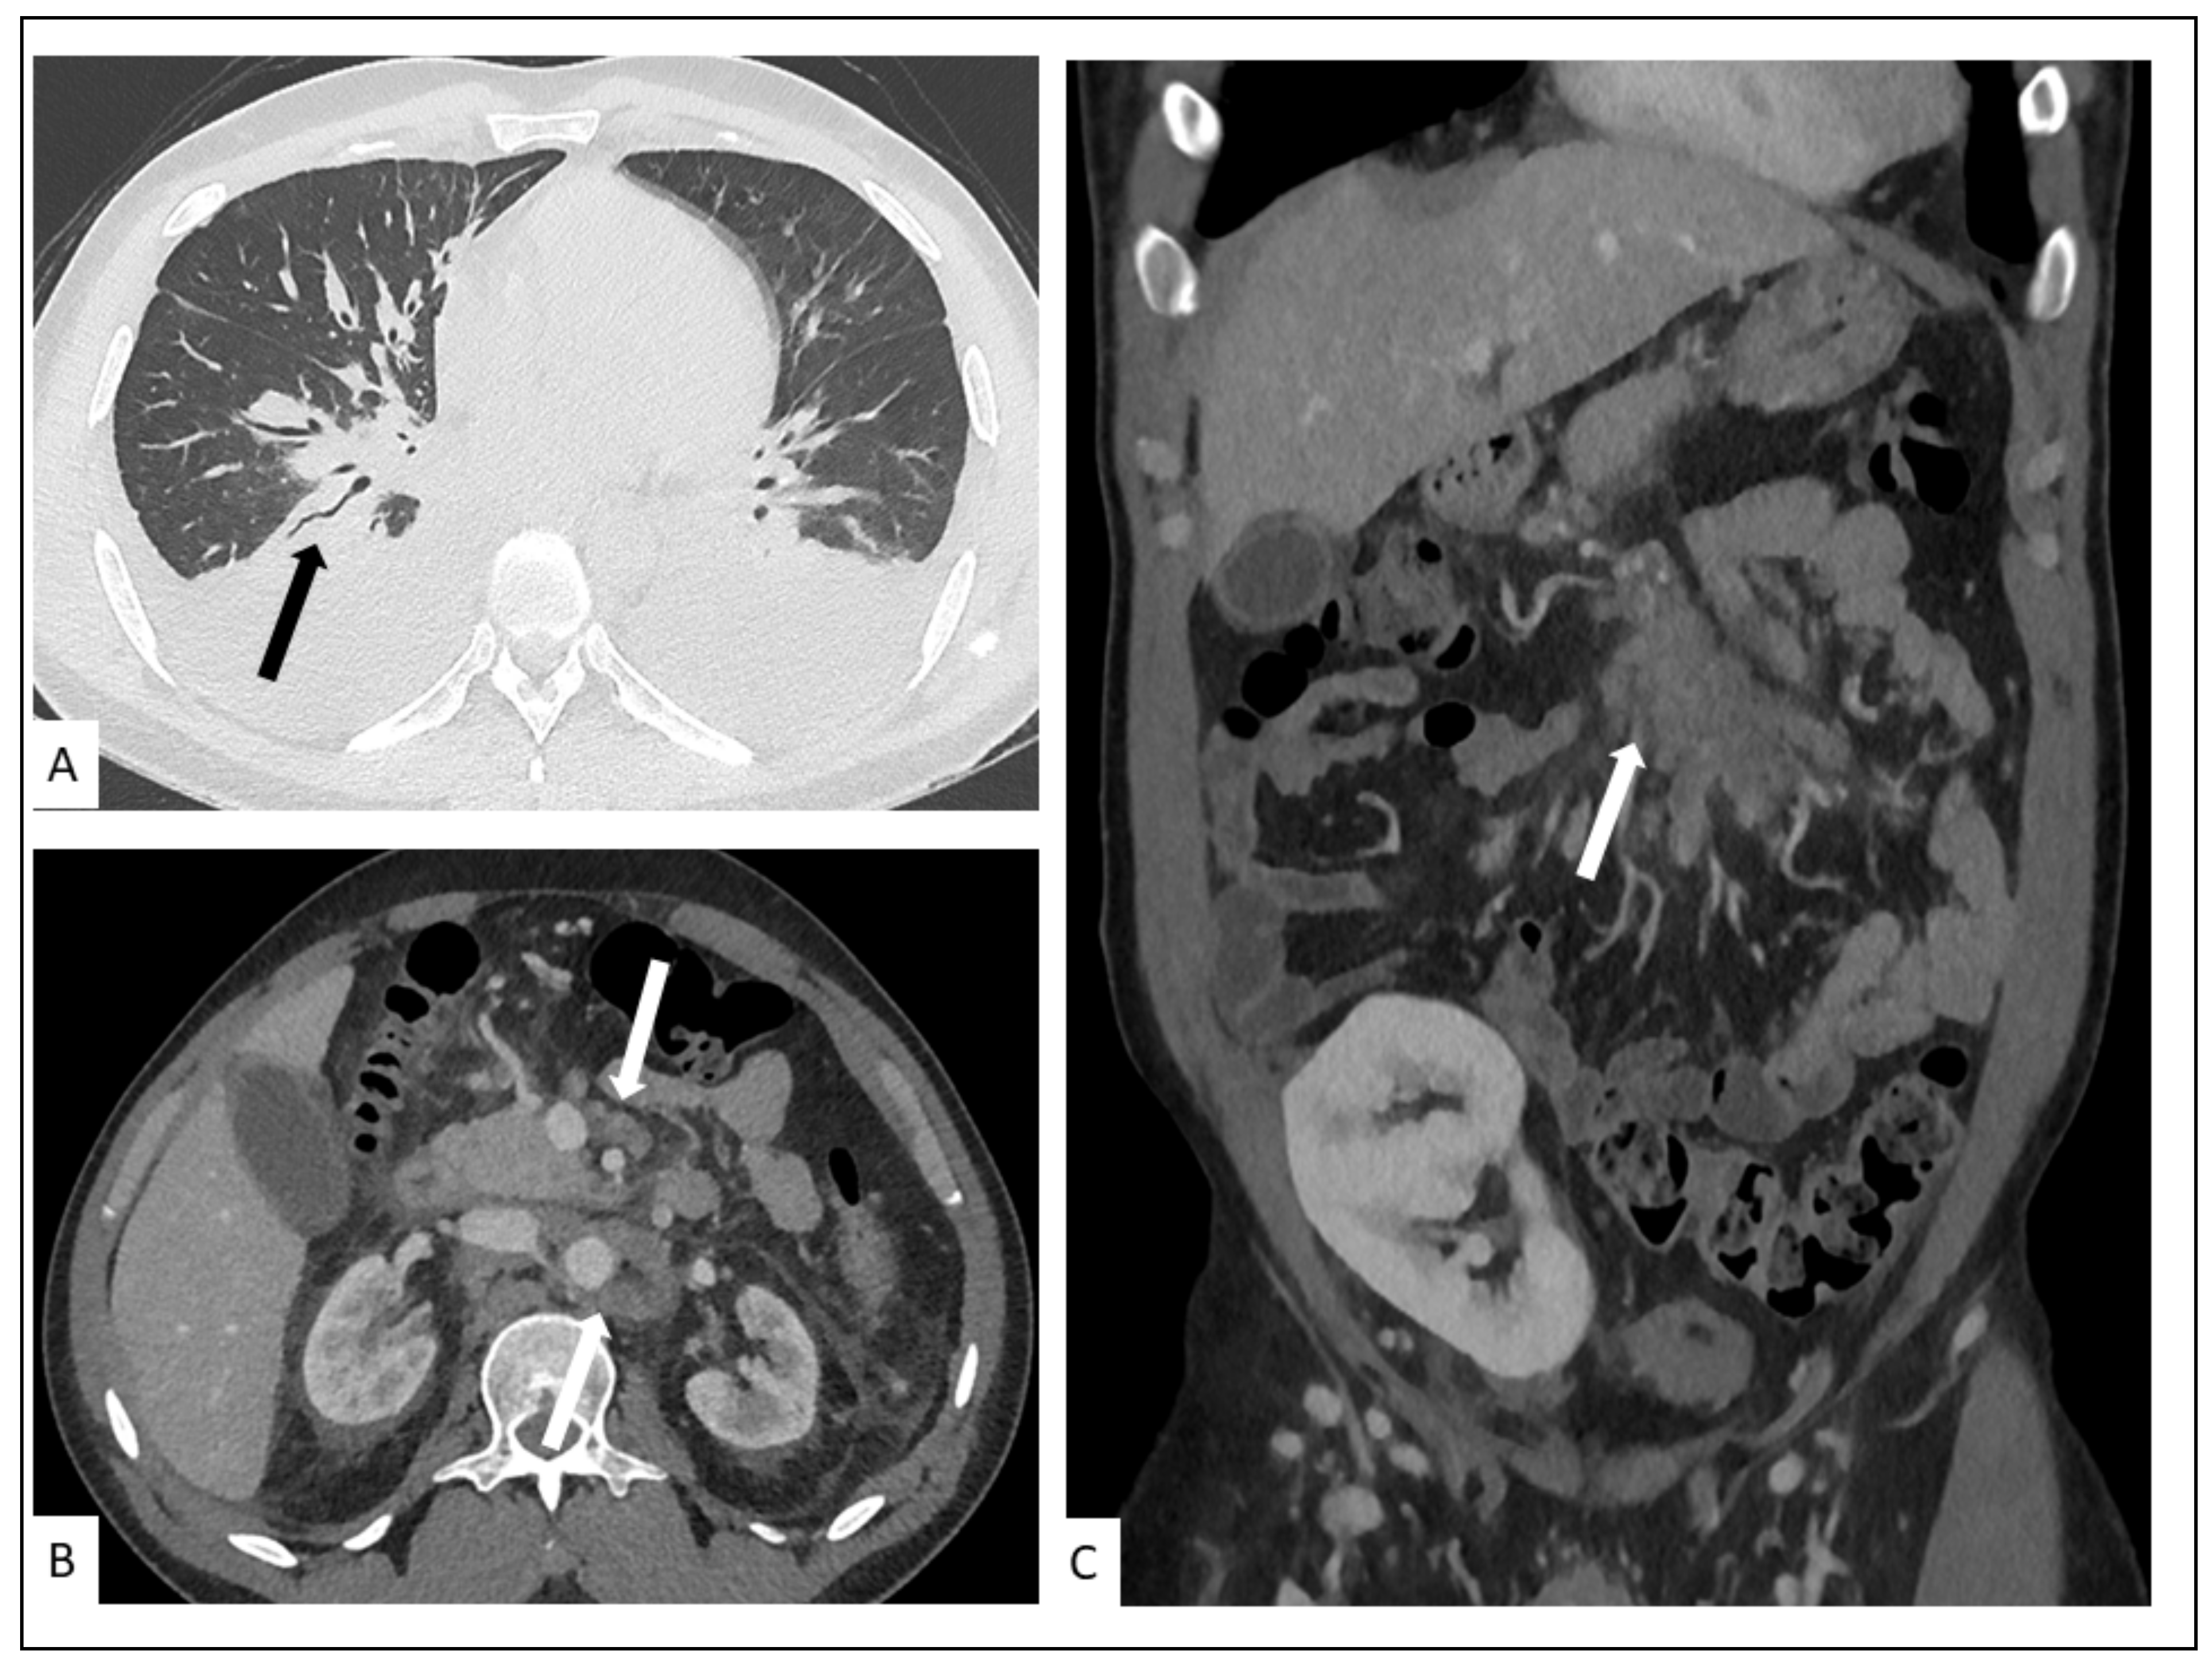

5.2. Hepato-Splenic KS

5.3. Other Visceral Involvement